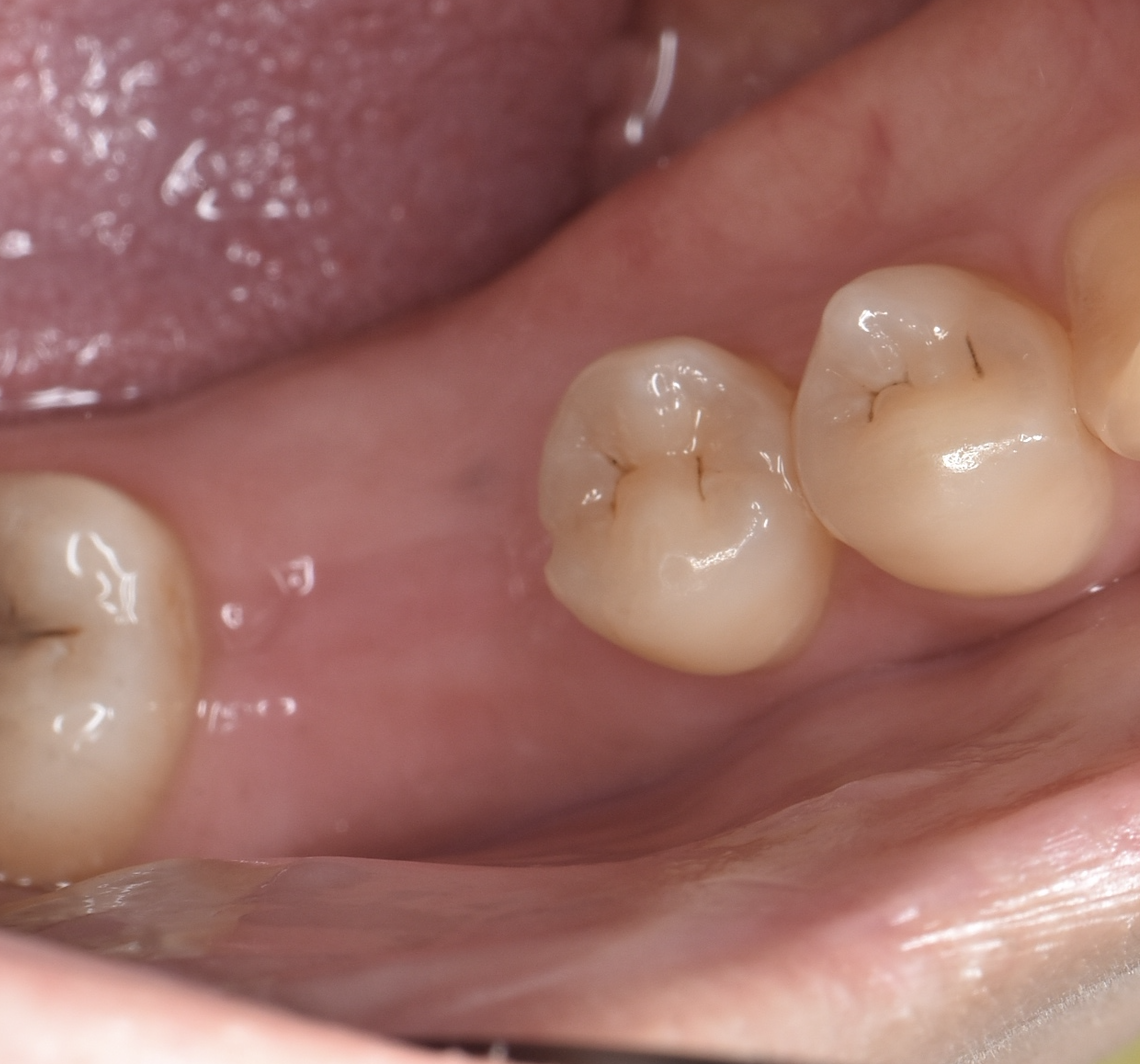

Before

40代男性 失った奥歯をインプラントで復元

治療期間:1年 費用:約100万円

デメリット:費用が高額 外科処置が必要

After

骨が薄い右側のみ抜歯と同時に骨を補う処置(リッジプリザベーション)を行い、骨が成熟するのを待ってインプラント埋入(*左右1番奥)